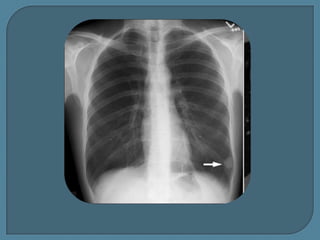

Radiografía simple (A) y TC (B) muestran una gran

masa maligna que mide más de 3 cm.